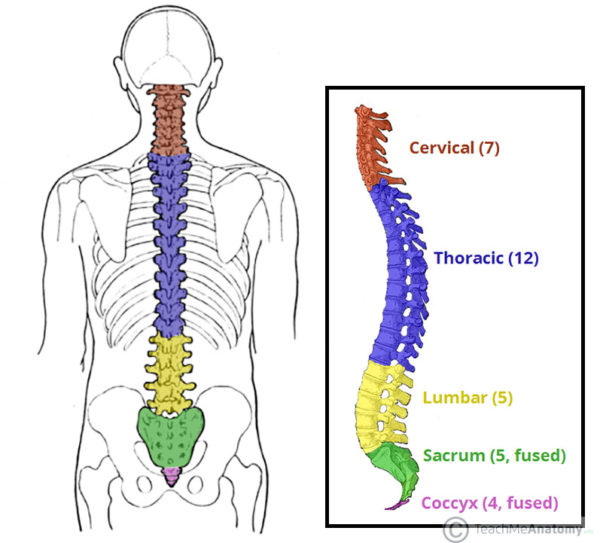

silikonsheet.blogg.se – Spine diagram

Anatomy of the Spine | Globus Medical

Anatomy of the Spine | Wessex Spinal Surgeon

Spine Anatomy and Back Pain – The Core Expert

human spine anatomy diagram